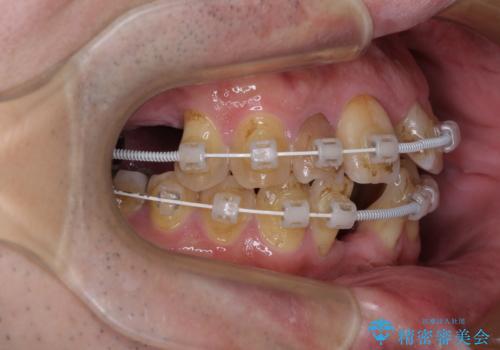

- 矯正装置

- 審美装置

- 治療期間

- 2年6ヶ月

- 治療回数

- 30回以上

矯正治療を行いながら、欠損部はインプラントによる補綴治療を希望されたため、補助装置を用いたワイヤー矯正によりスペースを確保しながら歯列を整え、適宜インプラントを埋入していくこととしました。